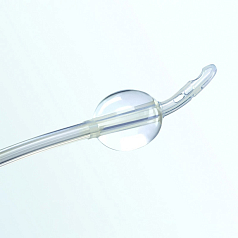

Трехходовые и двухходовые простатические катетеры используются в урологии после операций на предстательной железе.

Трехходовые и двухходовые простатические катетеры используются в урологии после операций на предстательной железе.